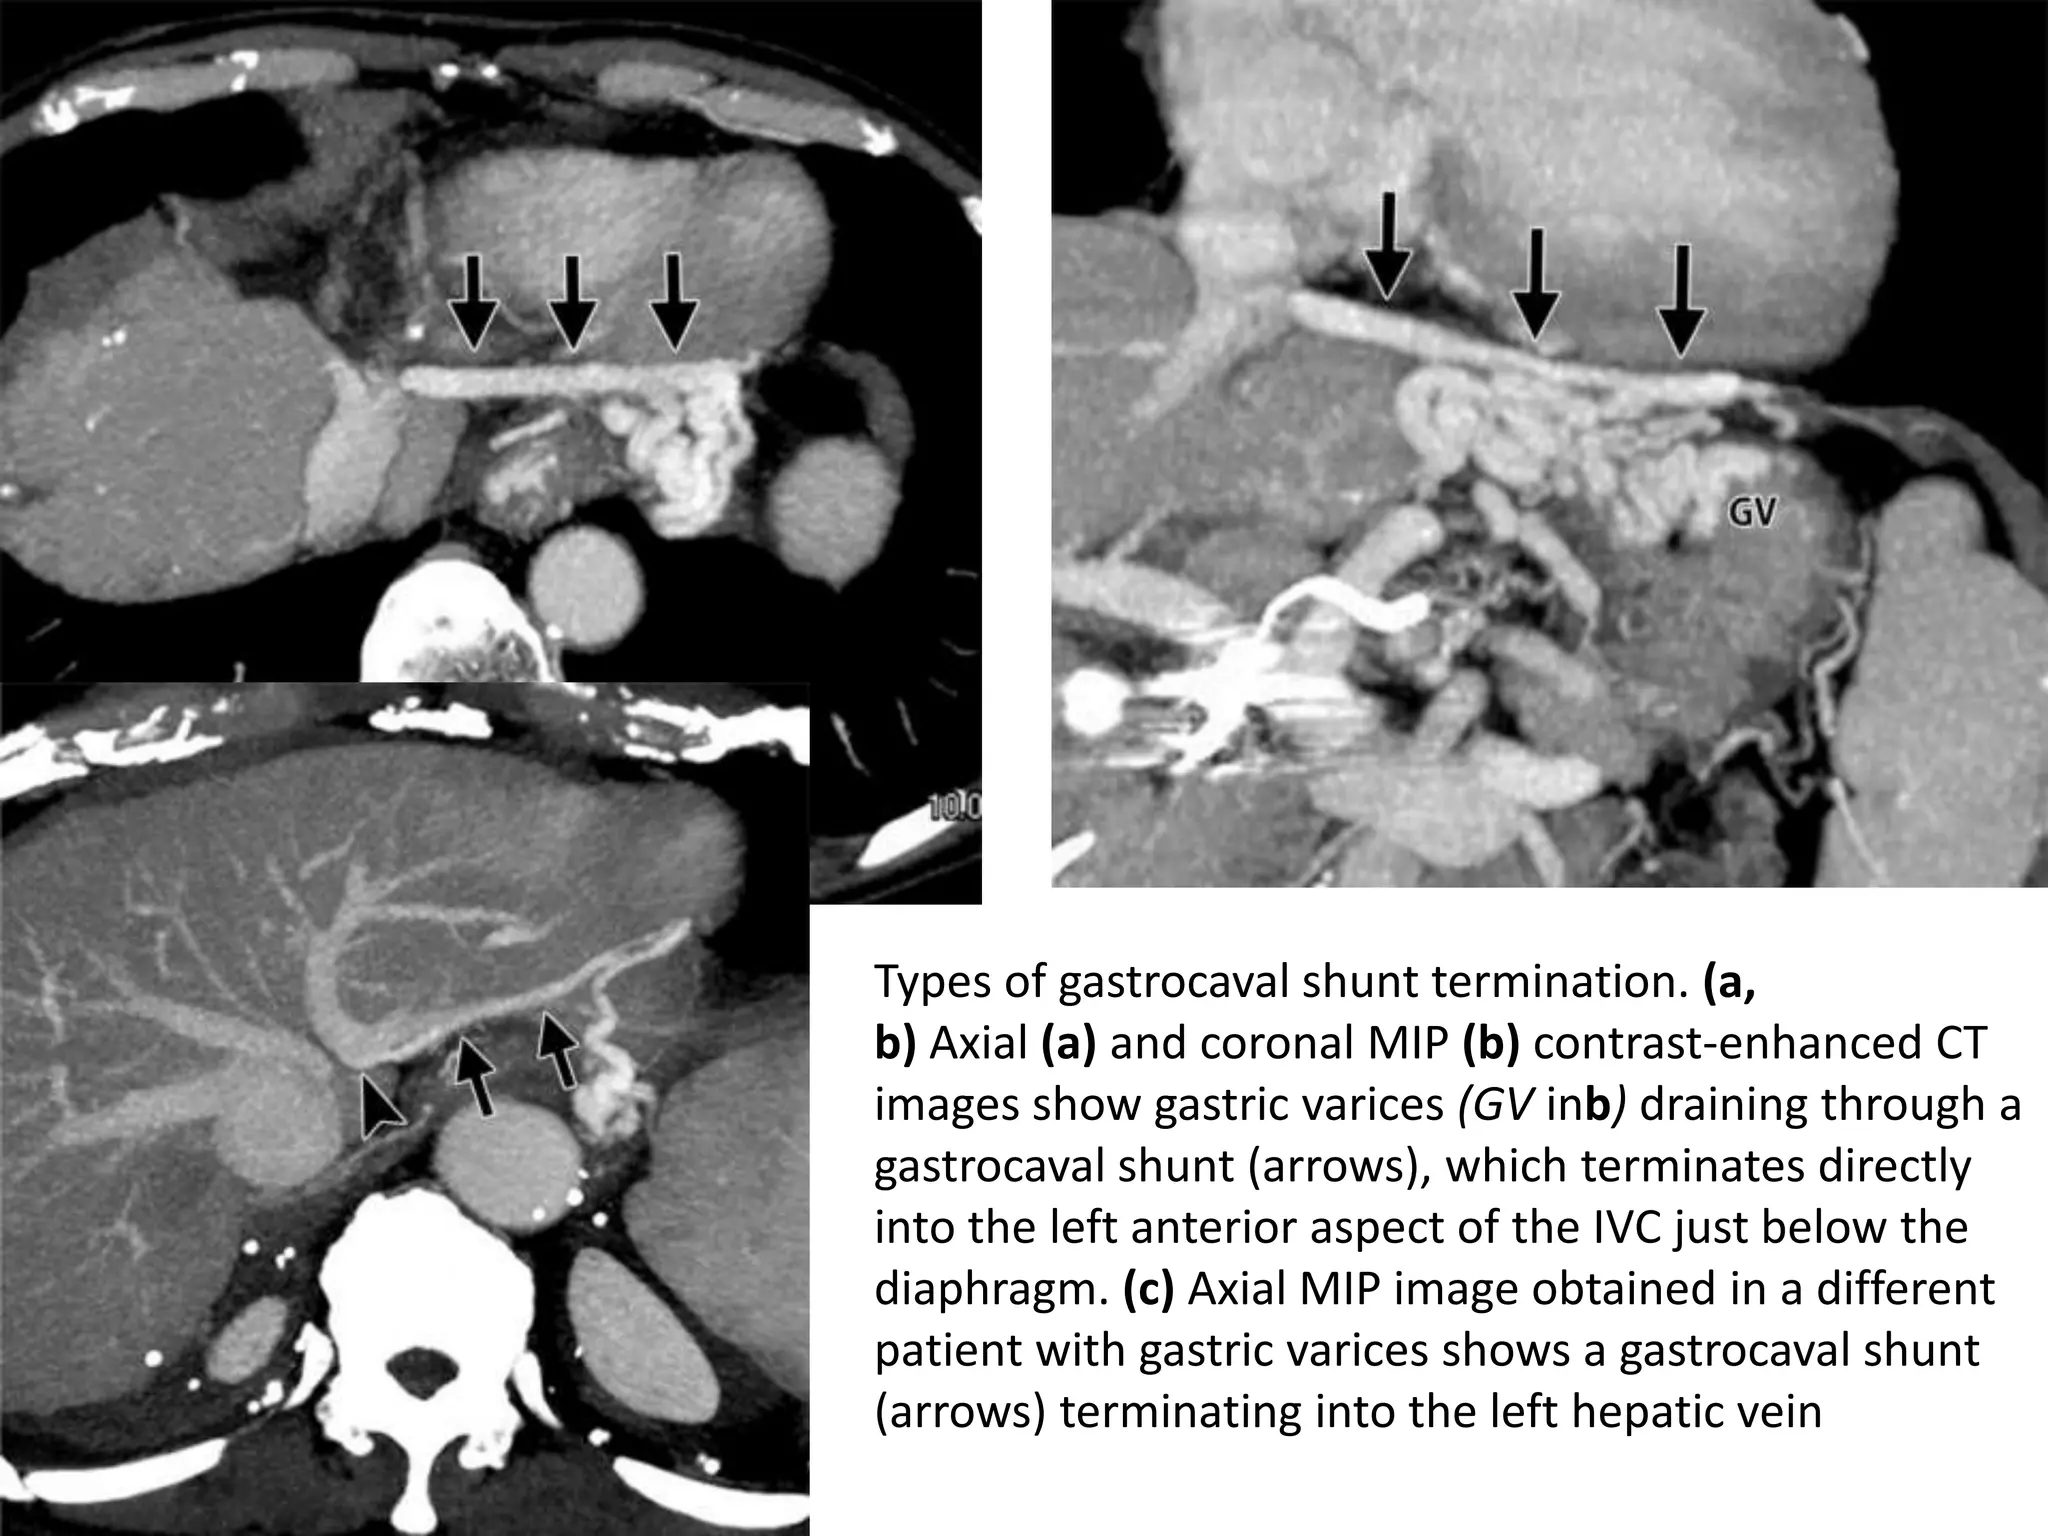

Types of gastrocaval shunt termination. (a,

b) Axial (a) and coronal MIP (b) contrast-enhanced CT

images show gastric varices (GV inb) draining through a

gastrocaval shunt (arrows), which terminates directly

into the left anterior aspect of the IVC just below the

diaphragm. (c) Axial MIP image obtained in a different

patient with gastric varices shows a gastrocaval shunt

(arrows) terminating into the left hepatic vein